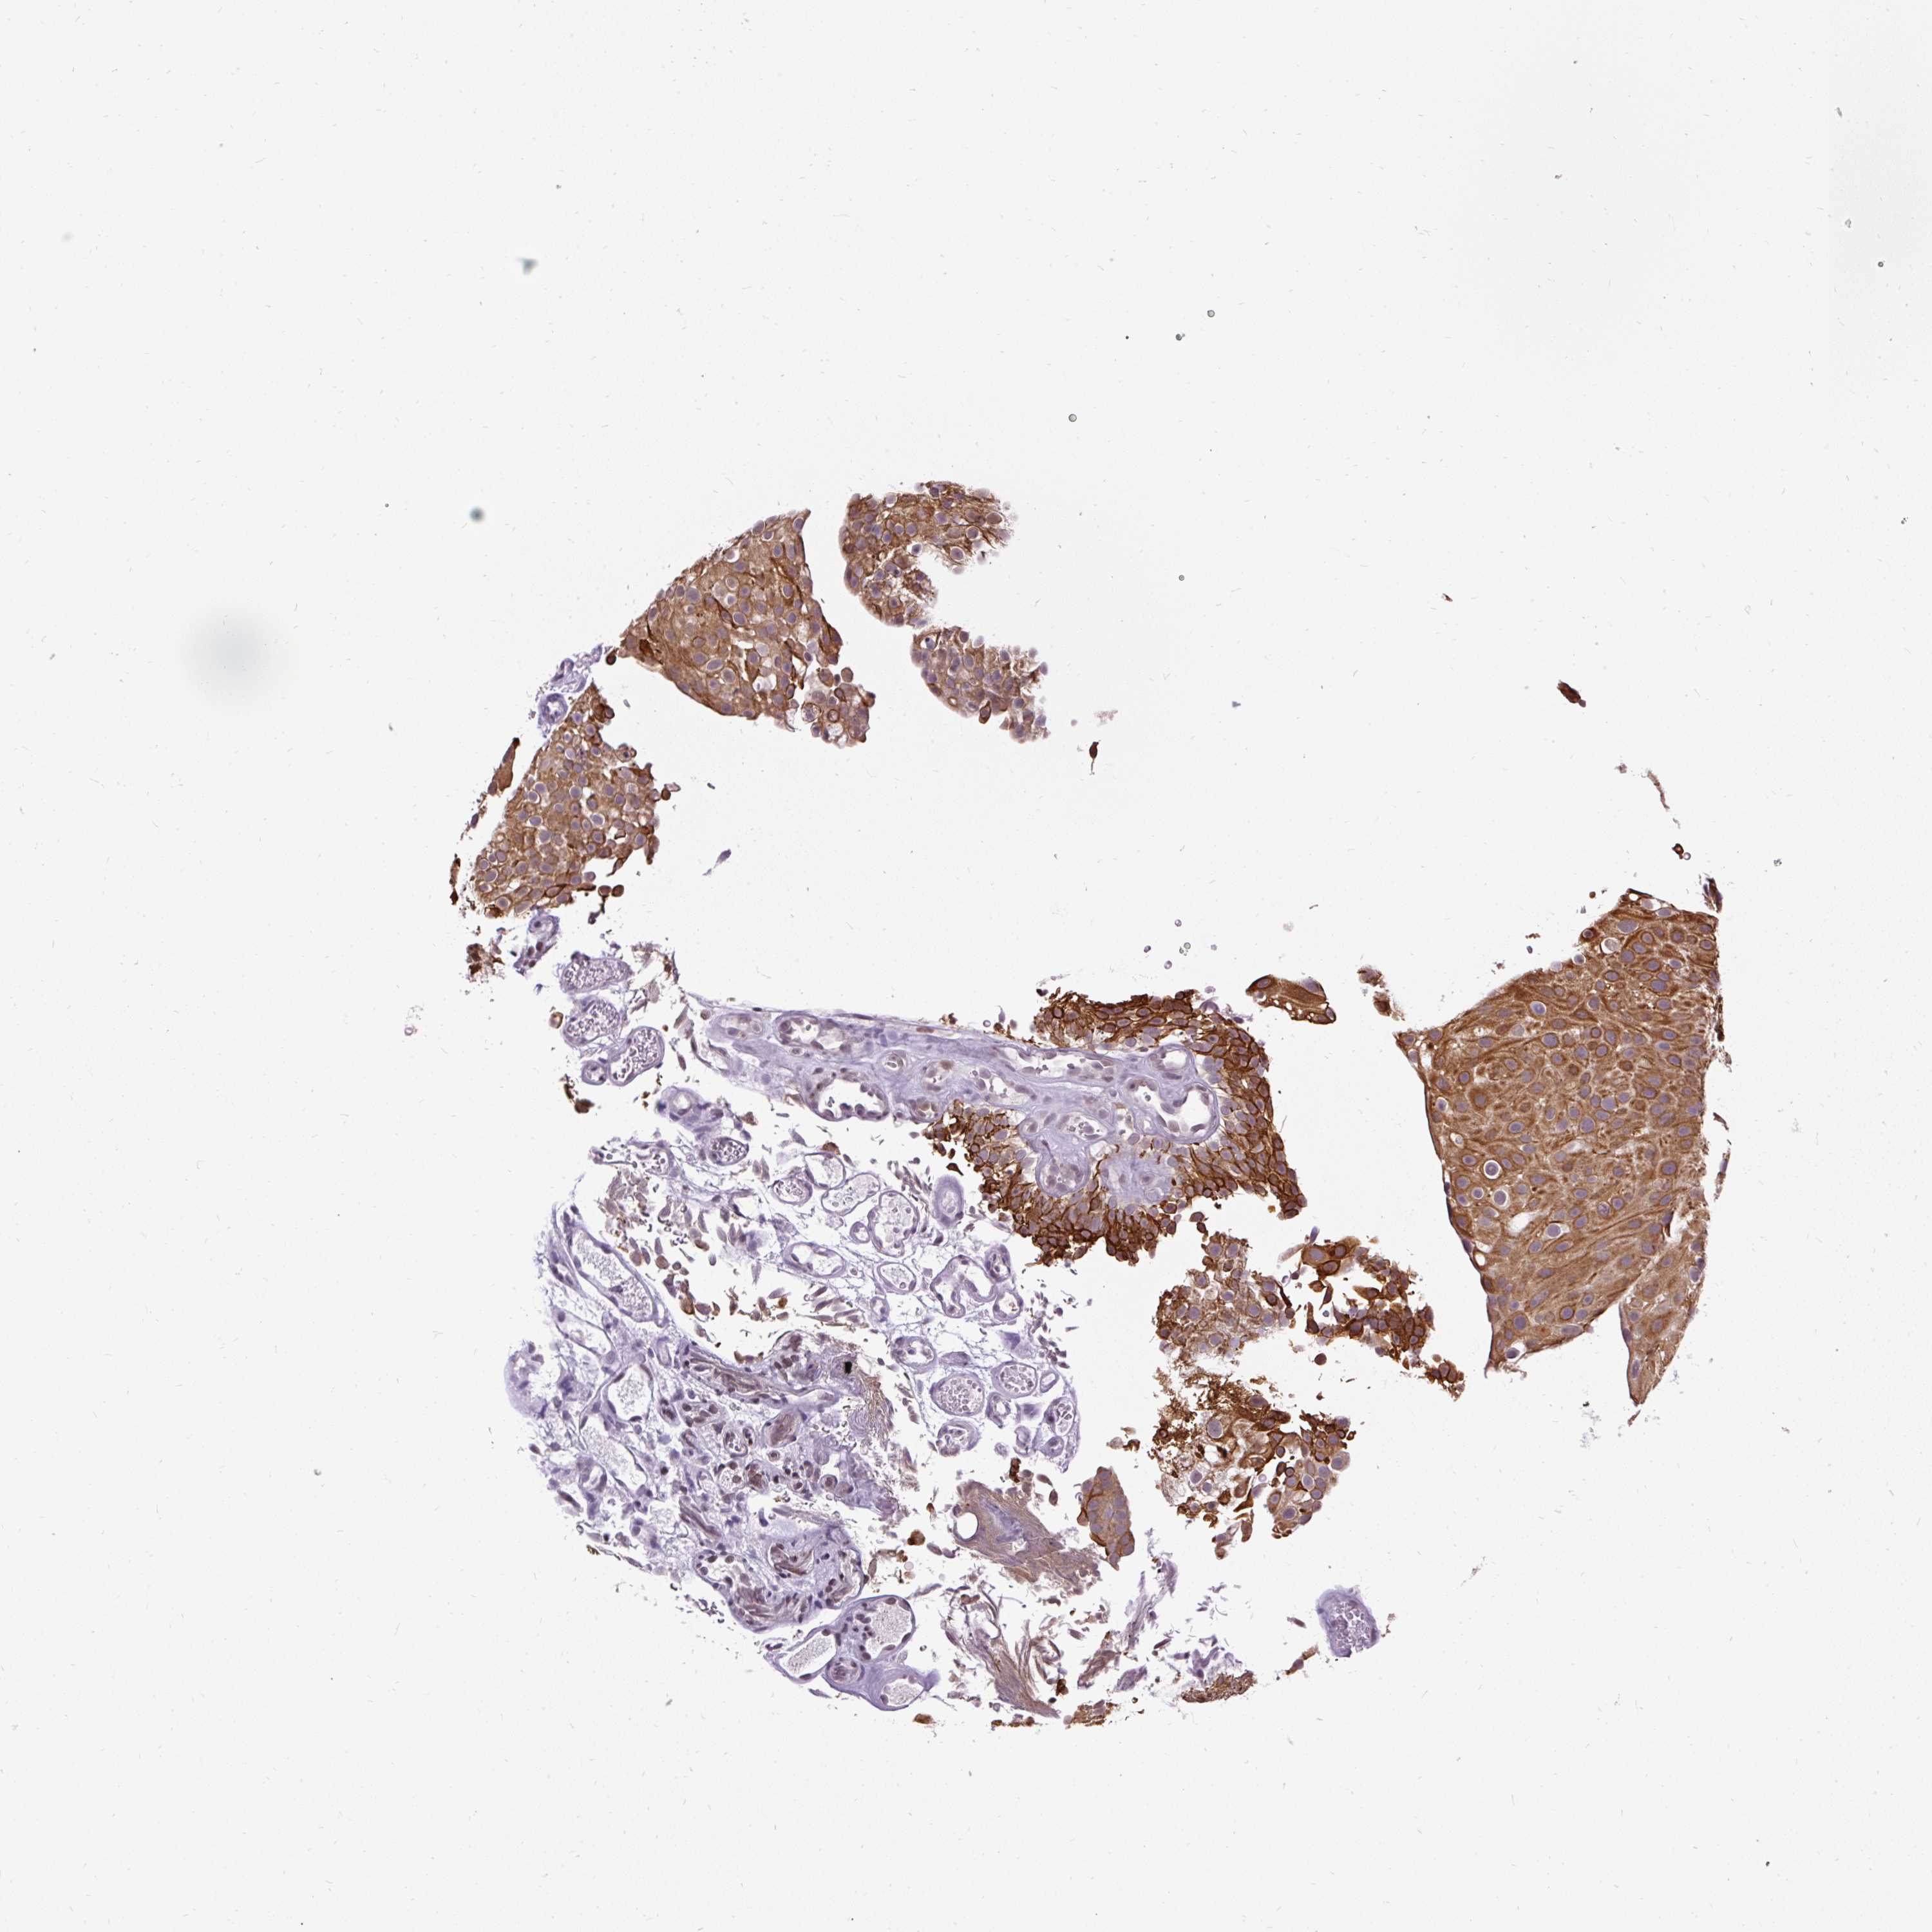

UROTHELIAL CANCER - Protein expressioni

A mouse-over function shows sample information and annotation data. Click on an image to view it in a full screen mode. Samples can be filtered based on level of antibody staining by selecting one or several of the following categories: high, medium, low and not detected. The assay and annotation is described here.

Note that samples used for immunohistochemistry by the Human Protein Atlas do not correspond to samples in the TCGA dataset.

Antibody stainingi

Antibody staining in the annotated cell types in the current human tissue is reported as not detected, low, medium, or high, based on conventional immunohistochemistry profiling in selected tissues. This score is based on the combination of the staining intensity and fraction of stained cells.

Each image is clickable and will lead to virtual microscopy that enables deeper exploration of all samples and also displays staining intensity scores, fraction scores and subcellular localization as well as patient and tissue information for each sample.

Antibody HPA055779

Staining

High

Medium

Low

Not detected

Intensity

Strong

Moderate

Weak

Negative

Quantity

>75%

75%-25%

<25%

None

Location

Urothelial carcinoma, High grade

Urothelial carcinoma, NOS

Urothelial carcinoma, Low grade